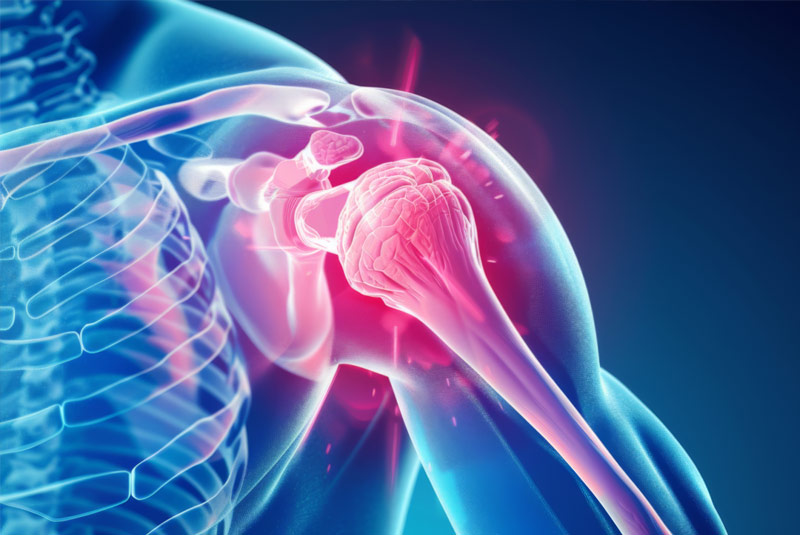

Έχει 5ετή μετεκπαίδευση και εργασία στο Ηνωμένο Βασίλειο ως ειδικός Ορθοπαιδικός Χειρουργός. Έχει εργαστεί στα Ορθοπαιδικά Τμήματα των Νοσοκομείων Southampton University Hospitals NHS Trust, Leeds Teaching Hospitals NHS Trust και στο Northampton General Hospital NHS Trust, με υποεξειδίκευση στη Χειρουργική Ώμου, Γόνατος, Ισχίου, Ποδοκνημικής & Άκρου Ποδός, Ώμου & Αγκώνος και Γενικού Τραύματος Ενηλίκων και Παίδων.

Κατά τη διάρκεια της εργασίας του στο Ηνωμένο Βασίλειο εκπαιδεύτηκε σε σύγχρονες τεχνικές Αρθροσκοπικής Χειρουργικής και Επανορθωτικής Χειρουργικής Ισχίου, Γόνατος και Ώμου. Επιπλέον έχει δώσει πολυάριθμες διαλέξεις και έχει εκπαιδεύσει νεότερους Ορθοπαιδικούς και φοιτητές Ιατρικής. Αξιοσημείωτο και πλούσιο είναι το επιστημονικό του έργο με συμμετοχή σε δεκάδες συνέδρια και σεμινάρια στην Ελλάδα και στο εξωτερικό και έχει πληθώρα προφορικών ανακοινώσεων και δημοσιεύσεων.

Παθήσεις & Θεραπείες